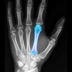

BoneGauge allows you to approximate an individual's bone density and quality from a mobile platform. BoneGauge helps you make measurements of cortical thickness of the second metacarpal from either hand or wrist x-rays. Use your smart phone camera to take a photo of the second metacarpal on an x-ray, or make measurements from an image saved in your photo library.

BoneGauge accurately calculates 2nd metacarpal cortical percentage (2MCP) in a semi-automated fashion. 2MCP has been shown to correlate with hip bone mineral density and T scores from DXA scans. Measurements made in the app will be uploaded to a central database. When combined with a patient's age, gender, and DXA score, past measurements will also help the improve the accuracy of future measurements.

This app allows you to estimate an individual's global T score in an office or hospital setting, by simply taking a photo of the 2nd metacarpal. While this measurement may not completely replace DXA, it may help a clinician screen a patient's bone quality to assist in treatment decisions and determine who may benefit from further bone density testing or osteoporosis treatment.